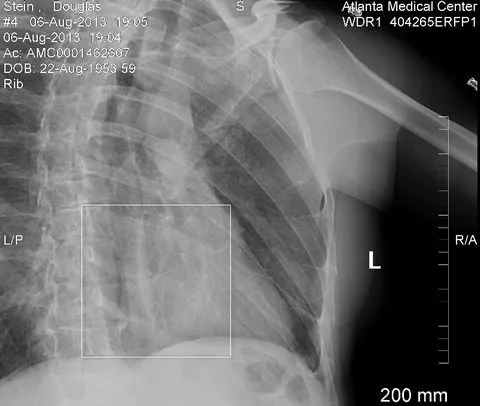

Any movement was painful, but this was exaggerated by the anxiety that I might have something injured INSIDE. When still, I was fine and my blood count was normal ... relief.

During typically long ER waits, we worked on this web page and updated family members by phone. Then I had a CT scan of the chest and abdomen.

All I had was broken ribs on the left side. We were cleared to return to Tampa, left the ER at 10 PM, and caught an 11:07 PM flight.

When not out of alignment, rib fractures can be difficult to find, but this one seems rather obvious.